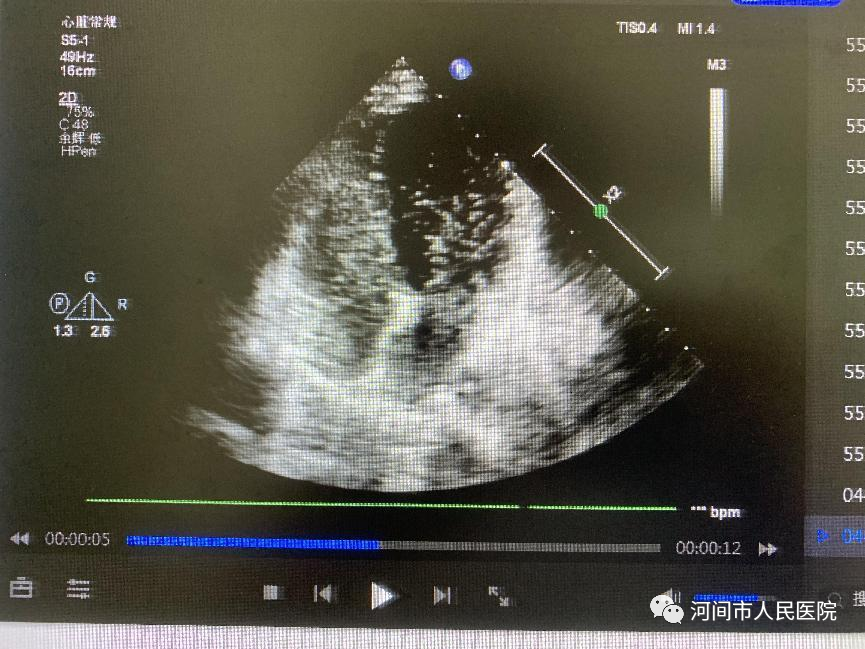

異常時心髒超聲左心內(nei) 出現微泡,TCD檢測大腦中動脈發現微栓子信號。